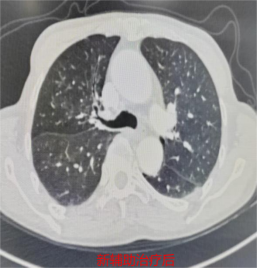

据悉,患者林先生(化名)4个月前在外院被确诊为右肺上叶肺门处鳞癌(IIIA期),后转诊至宁德市医院胸心外科接受进一步治疗。宁德市医院胸部肿瘤多学科团队(MDT)首席专家、胸心外科主任医师何昌进牵头,结合患者高龄、身体基础状况及肿瘤分期,为其制定了新辅助治疗联合手术的个体化方案。经过4个周期的新辅助治疗,林先生复查显示肿瘤显著缩小,达到手术指征。

辅助治疗前影像图。宁德市医院供图